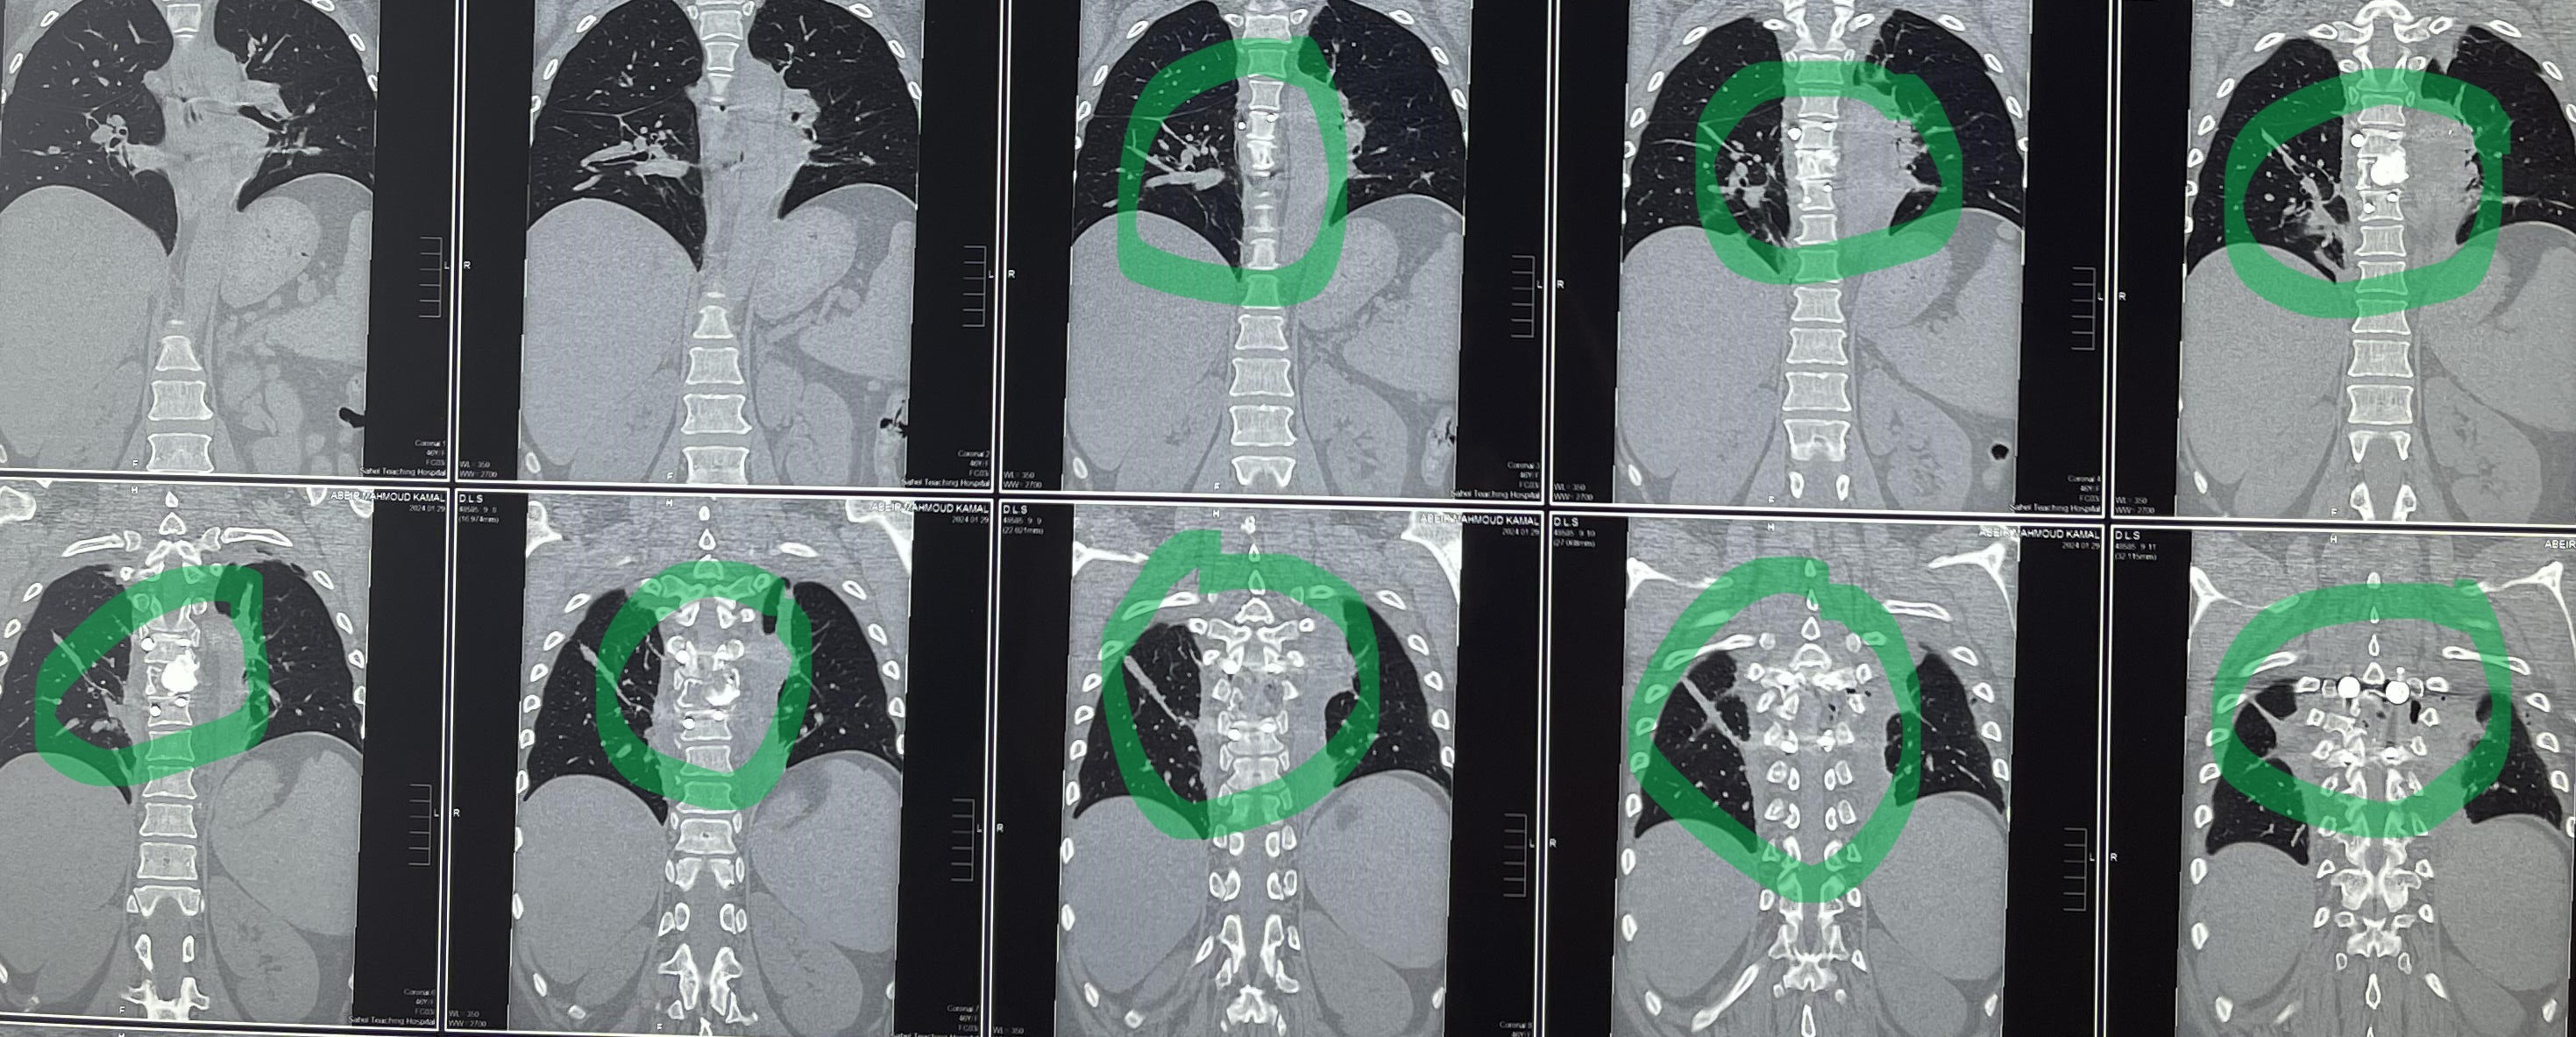

مريضة عمرها 43 عام تعاني من ضعف متزايد بالطرفين السفليين.

43-year-old female patient suffers from increasing weakness in the lower extremities

A 43-year-old woman suffering from progressive weakness in both lower limbs was diagnosed and treated. This condition affects walking ability and mobility, requiring thorough neurological evaluation to determine the underlying cause and develop an appropriate treatment plan.

• Accurate diagnosis using latest neuroimaging techniques

• Continuous monitoring to assess progress